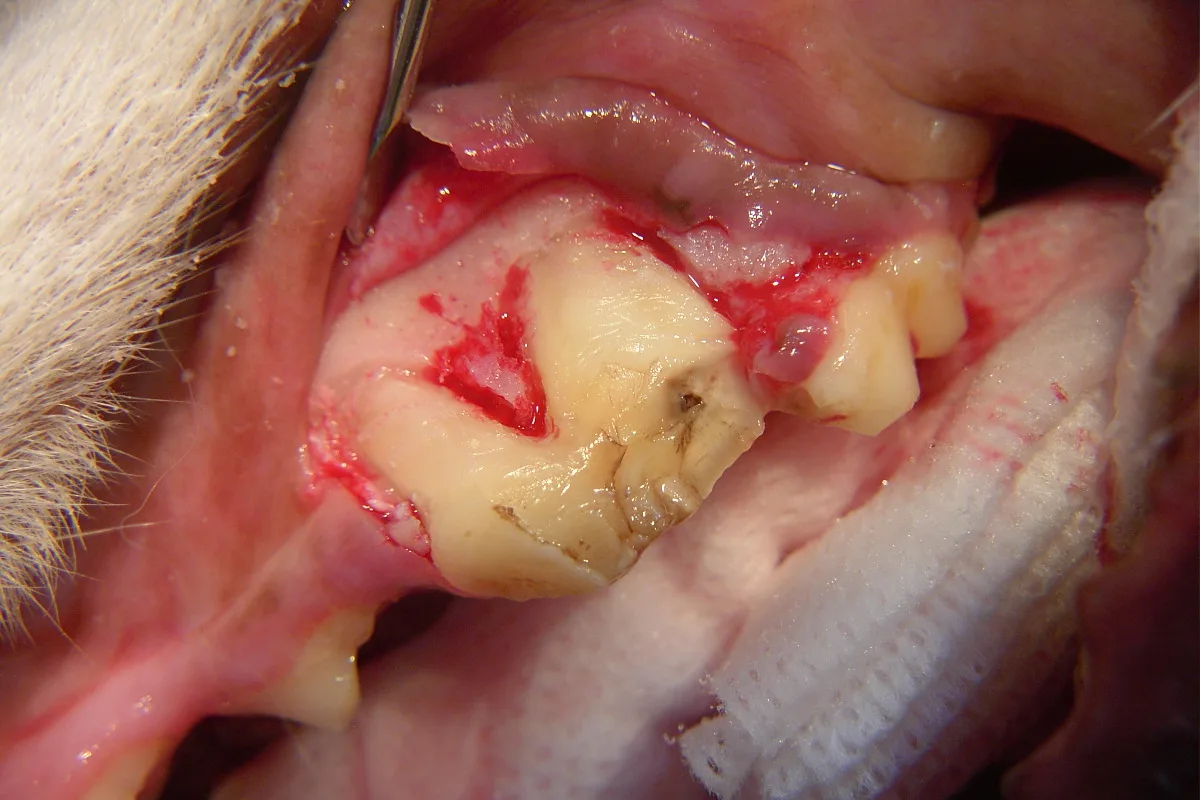

The following steps address surgical extraction of a fractured maxillary left 4th premolar tooth (#208).

Step 1

A full thickness mucoperiosteal gingival flap is planned (indicated by the dotted line). Important surgical anatomy includes the parotid and zygomatic salivary ducts at the distal (caudal) aspect of the affected tooth and the infraorbital neurovascular bundle, which is mesial (rostral) to the vertical incision location.

Step 2

The vertical incision is made starting 5 mm apical to the mucogingival line at the mesial aspect of the left maxillary 4th premolar tooth, with firm pressure along the mesial aspect of the alveolar juga of the mesiobuccal root, and continues ventrally to the gingival attachment at the crown. The incision is then extended horizontally within the gingival sulcus, deep enough to reach the alveolar crestal bone, and along the buccal surface of the tooth to the distal aspect of the maxillary 4th premolar. If more surgical exposure of the buccal bone (over the distal root) is needed, the incision can be extended to the distobuccal line angle of the maxillary 1st molar (as is depicted in this and the following steps).5-7 In addition, the remaining epithelial attachment is also incised circumferentially around the maxillary 4th premolar.